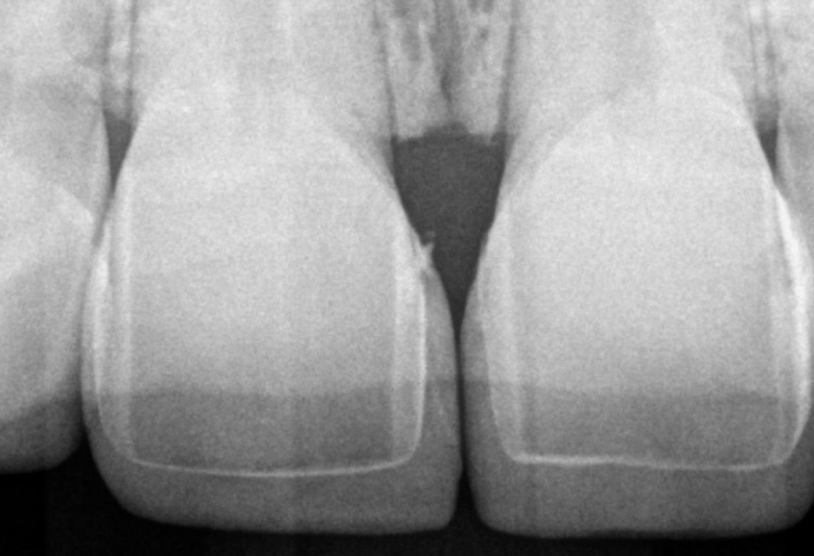

Close-up of teeth

Initial situation in the static occlusion.